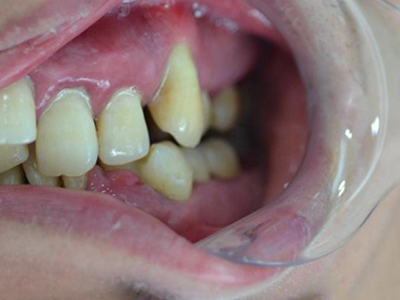

慢性龈炎的病损部位一般局限于游离龈和龈乳头,以前牙区为主,尤其以下前牙区最为显著,患者常因刷牙或咬硬物时牙龈出血而就诊。游离龈和龈乳头颜色变为鲜红或暗红色,病变较重时炎性充血可波及附着龈。龈缘变厚,龈乳头圆钝肥大,可增生呈球状,覆盖牙面。牙龈松软脆弱,缺乏弹性。

当牙龈以增生性反应为主时,龈缘和龈乳头呈坚韧的实质性肥大,质地较硬而有弹性。龈沟液量增多,还可能出现龈沟溢脓现象。